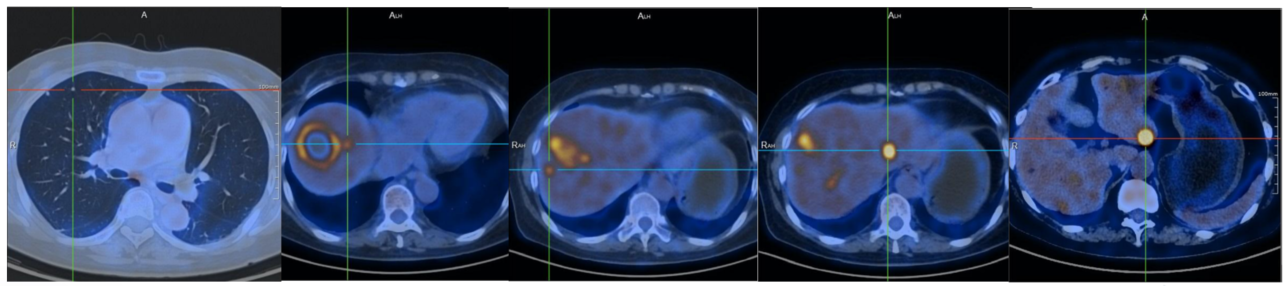

2021.09.07:术后PET/CT提示,1.乙状结肠MT术后、肝转移性MT消融术后:肝右叶前上段团块状混杂密度影,边缘伴糖代谢增高,最大SUV值为8.38,大小约为43.2*31.4mm考虑为治疗后改变可能,请结合临床;肝内多发伴糖代谢增高的结节状低密度影,最大SUV值为19.69,大小约为 17.9*15.6mm,考虑为转移;双肺多发不伴糖代谢增高的实性结节影,转移不除外。吻合口局部肠壁伴糖代谢稍升高,考虑为炎症改变可能性大;2.双侧甲状腺良性结节;3. 肝右前叶上段不伴糖代谢增高的结节样低密度影,考虑为良性改变可能性大,建议随诊,肝内多发囊肿;胆囊炎;左肾囊肿;左肾结石;子宫肌瘤;腹膜后腹主动脉及下腔静脉间、双侧腹股沟反应增生型淋巴结;5.骶管囊肿(图1)。